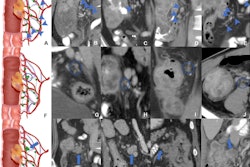

When it comes to challenging cases involving facial trauma, CT rules supreme. That’s the view of researchers from San Sebastián in Spain who won a top award at ECR 2025 for their work in this area.

In today’s top story, you can read about the team’s approach and how it obtained the stunning set of clinical images on display at the Vienna congress.